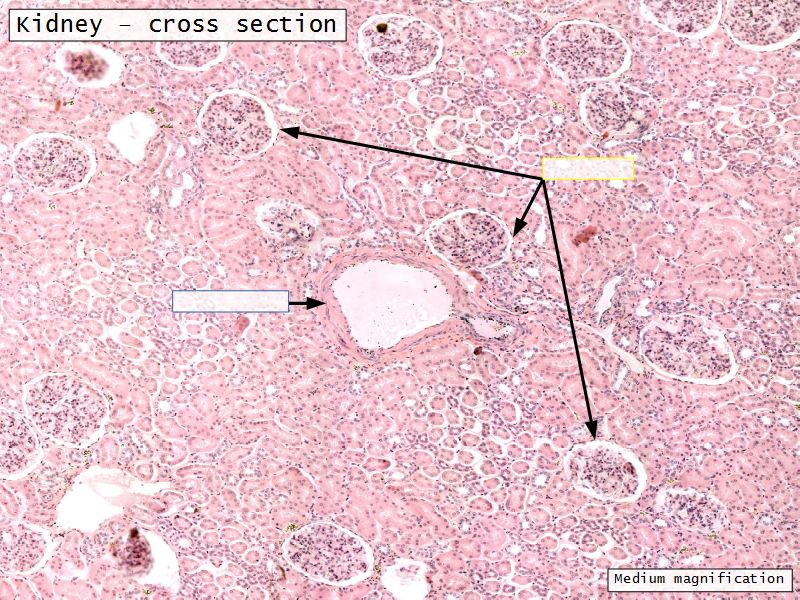

Appearance

- Cortex

- Renal corpuscles

- Convoluted tubules

Renal corpuscle

- Tuft of capillaries

- grow into

- Blind end of nephron

- Several layers of epithelium

- Two sides

- Vascular pole

- Tubular pole

Blood flow

- Efferent arteriole

- Smooth muscle in media

- Capillaries

- Fenestrated

- Afferent arteriole

- Smooth muscle in media